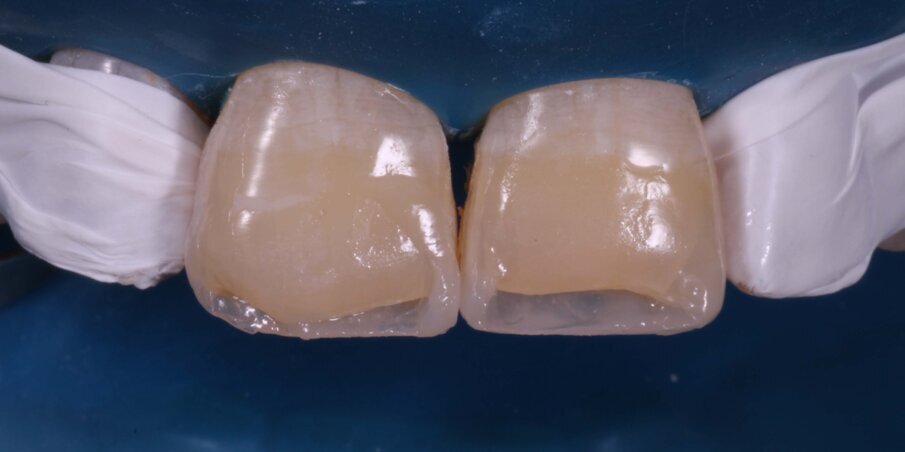

Direct Composite restorations of 11 and 21 to restore the correct length of the incisors, thereby changing the reverse to a consonant smile line. The patient refused treatment for 12 for the time being. Polychromatic layering technique would be used for the composite resin stratification (Fig 6).

Fig 6: Shade matching